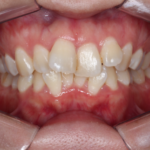

【叢生】インビザライン症例:ガタガタが気になる

治療前 治療後 症例の詳細 主訴 ガタガタが気になる ...